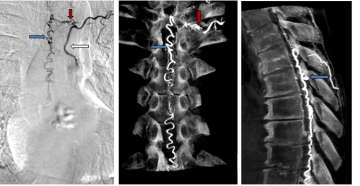

- Spinal angiogram – This exam is the gold standard for confirming the presence of a spinal vascular malformation, characterizing the malformation, and demonstrating its exact location in the spinal canal (Figure 3). This imaging study is used to best understand the anatomy of the malformation so the appropriate treatment option can be determined.

- Surgery – many spinal vascular lesions are best treated with surgery and can be cured with low risk to the patient (Type I lesions). A spinal angiogram is typically needed prior to surgery in order to guide the surgeons to the abnormal vessels. Surgery typically involves a small incision in the back, in order to disconnect the vascular abnormality (Figure 4).